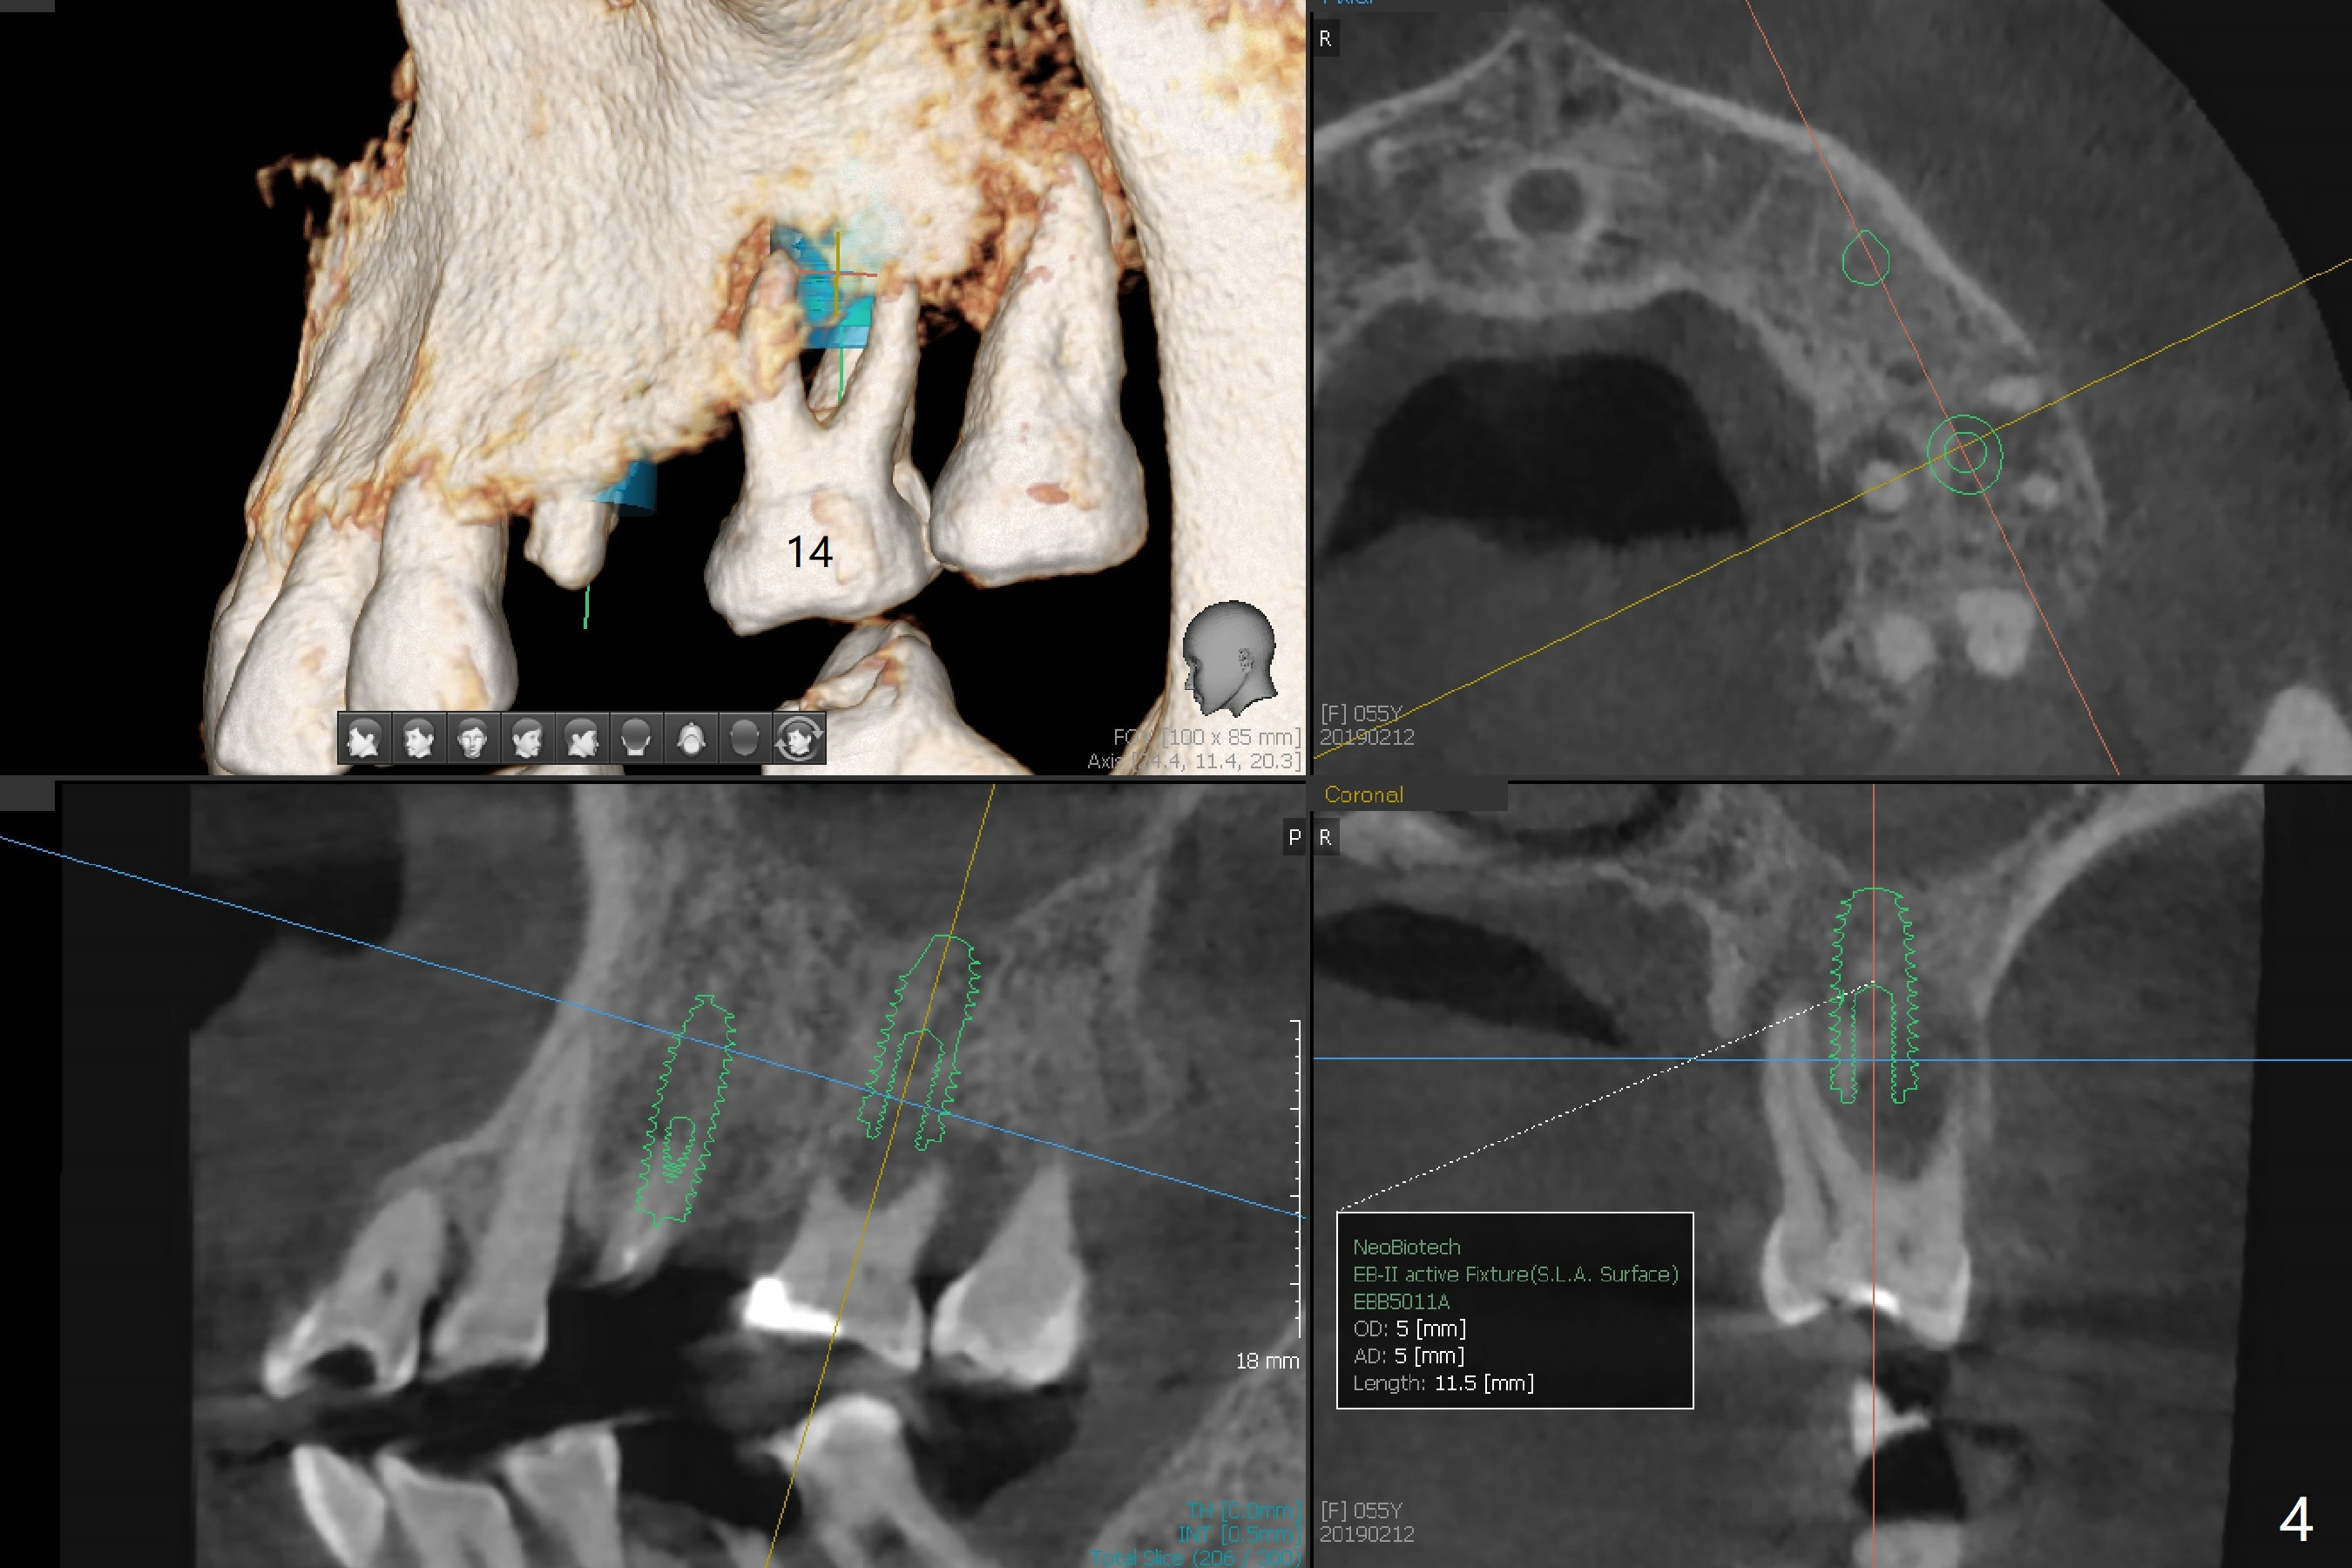

A 55-year-old woman has poor dentition, which is partially related to her previous history of ice chewing (Fig.1). The long bone height in the jaws suggests bruxism and requires as many teeth and implants as possible. After SRP, caries will be removed from #14 and 15 for determination of salvageability (Fig.2). The patient prefers to save the tooth #30. Endo referral will be recommended for #14 and 30. If the tooth #14 proves to be nonsalavageable, it will be extracted with #12 for immediate implants and subsequent FPD (Fig.3,4). Immediate implant will be avoided at #19 due to severe bone loss. Instead a short implant (5.5x5 or 6 mm) will be placed at #18, while a 4x11.5 mm one at #20 for FPD (Fig.5,6). All of the implant will use guides. There is a special point at #18. After use of 4.5 mm drill, the guide will be removed for free hand osteotomy using 5.0 mm drill, 5.5 mm tap and implant placement. PRF will be prepared for membrane and sticky bone at #19 and 20. For the lower right quadrant, treatment for #30 should be conducted first, either RCT or implant. The tooth #29 will be uprighted using #30 as an anchor, if the former is salvageable. The implant at #28 will be placed last (Fig.7,8).